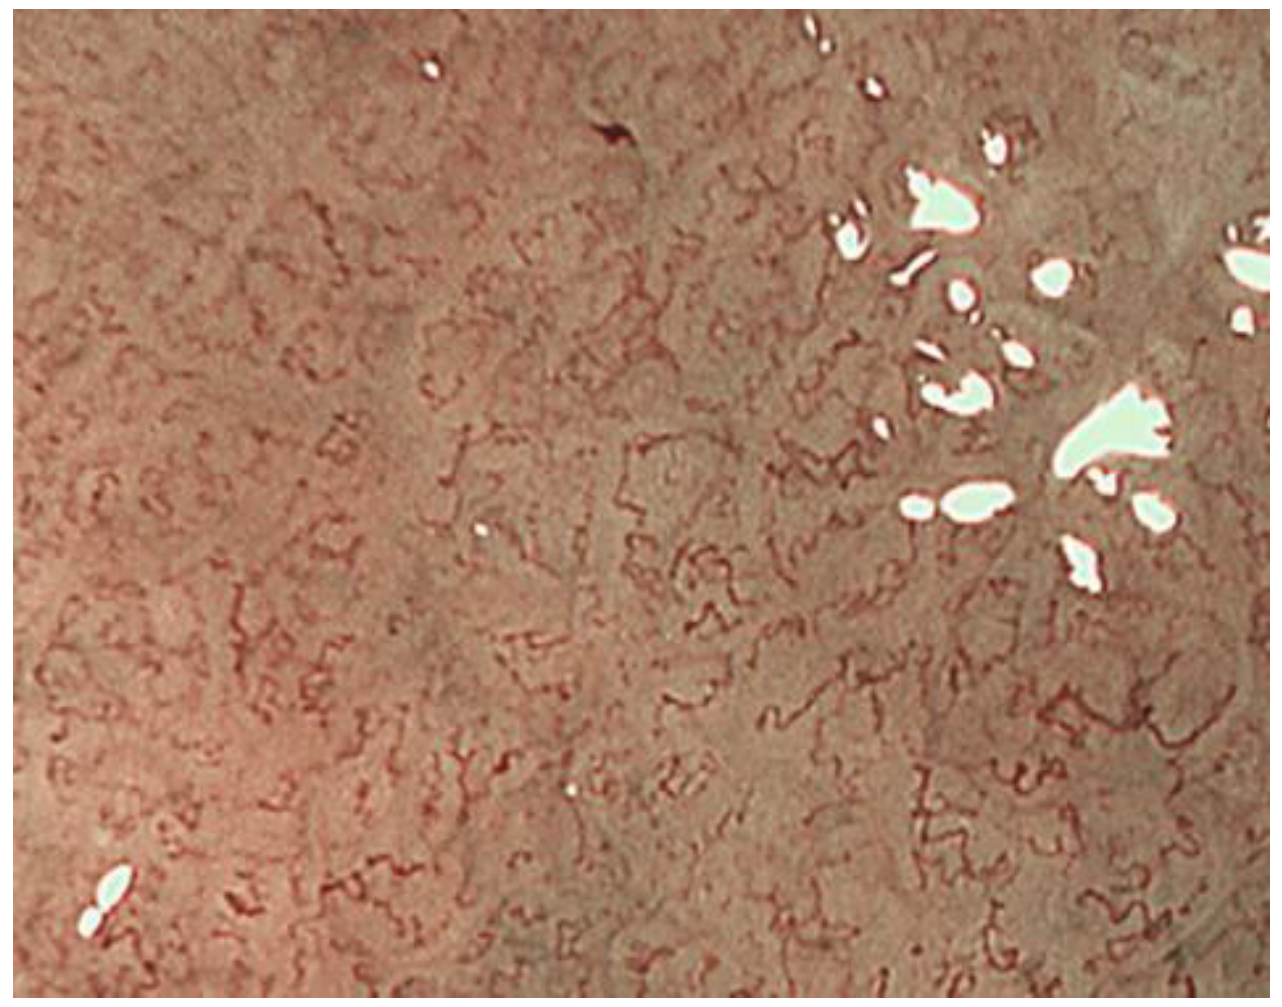

2.3. Inference of Histopathological Type of Gastric Cancer by ME-NBI